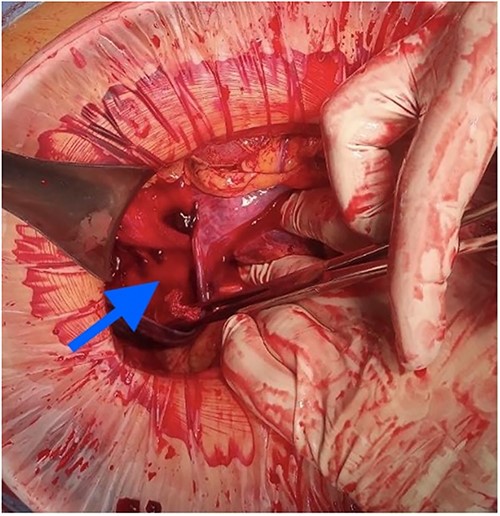

At laparotomy, it was apparent that a large hematoma had occupied the anterior aspect of the stomach causing extensive serosal stretch from fundus to pylorus (Fig. 4). Serous membrane under hematoma was ruptured and about 500 ml of hemorrhagic liquid with clots was detected in the peritoneal cavity. Serous membrane rupture was widened, evacuated blood clots and revealed small branch of left gastric artery as origin of bleeding (Fig. 5). Suture ligation of artery was performed. Surgery finished by drainage of abdominal cavity, cavity of hematoma with serous membrane suturing, and microjejunostomy for post-operative nutritional support.